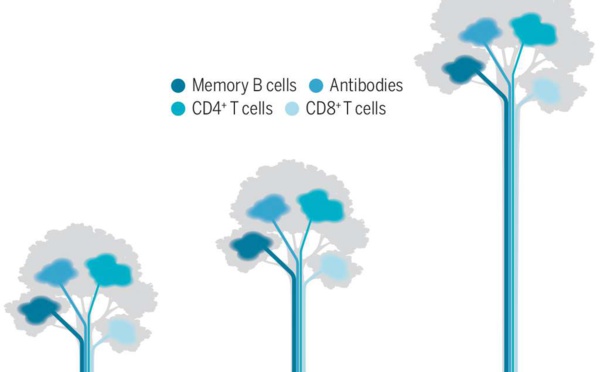

Contre le Covid-19 comme contre toutes les maladies infectieuses, on est protégé quand on est immunisé. Mais comment acquiert-on cette immunité ? De deux façons : soit en étant contaminé par le germe à l'origine de l'infection, soit en se faisant vacciner. La première situation correspond à...

Jusqu'à présent, la vaccination semblait être l'arme la plus efficace pour lutter contre la Covid-19. Une nouvelle publication américaine suggère que la protection des vaccins chute de manière radicale, et ce seulement quelques mois après la vaccination. Une étude publiée dans la prestigieuse...